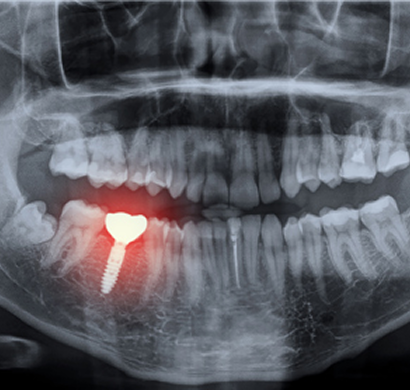

Cone Beam Computed Tomography (CBCT) is an advanced and highly precise 3D imaging technology used to visualize detailed structures of the teeth, jaw, face, and surrounding areas. It provides high-resolution, three-dimensional images that allow doctors to accurately assess bone structure, soft tissues, nerves, and airways, making it an essential tool in modern diagnostic and treatment planning.

Unlike traditional X-rays, CBCT captures multiple images from different angles and reconstructs them into a comprehensive 3D view. This enables better evaluation of complex anatomical structures that cannot be clearly seen in standard 2D imaging. CBCT is widely used in dental, maxillofacial, and ENT applications, helping in procedures such as dental implant planning, orthodontic assessment, root canal evaluation, jaw disorders, sinus analysis, and trauma cases. One of the key advantages of CBCT is its ability to provide highly accurate and detailed images with relatively lower radiation exposure compared to conventional CT scans. The scan is quick, painless, and typically completed within a few minutes. During the procedure, the patient simply stands or sits still while the machine rotates around the head, capturing precise images without discomfort.